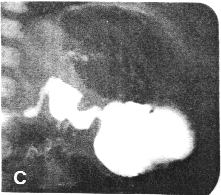

Case 20.3. B.F., 7 day old female infant presented with persistent, bile-stained vomiting since birth. Radiological study showed a tubular narrowing 2.0 cm in length in the pyloric region (Fig. 20.3). It conformed to partial contraction of the pyloric sphincteric cylinder with a prominent impression of the pyloric muscle knot on the lesser curvature side. There was total absence of cyclical contraction and relaxation of the cylinder, the pyloric aperture being fixed in the open or patent position. The duodenal cap was normal but there appeared to be some narrowing of the remainder of the first part of the duodenum. Infantile hypertrophic pyloric stenosis could not be excluded. Laparotomy revealed partial obstruction at the duodeno-jejunal junction due to ectopic pancreatic tissue in the intestinal wall and adhesions. The pylorus showed no organic lesion. After biopsy, severance of adhesions and pyloromyotomy, recovery was complete. The pyloric narrowing was diagnosed as spasm of the sphincteric cylinder.

| Fig. 20.3 A-D. Case B.F. Constant contraction of sphincteric cylinder. At operation no pyloric lesion was found | |